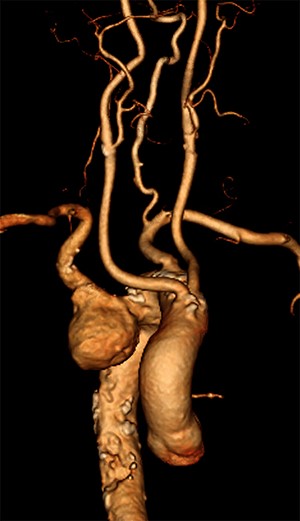

CT reconstruction illustrating a debranched left common carotid artery and subclavian artery with double coronary artery bypass graft (left internal mammary artery to left anterior descending, and saphenous vein T graft to obtuse marginal artery).

The initial procedure, performed via a median sternotomy, involved debranching the left common carotid artery (CCA) and left SCA with simultaneous double vessel CABG (left internal mammary artery to left anterior descending, and saphenous vein T graft to obtuse marginal artery) (Fig. 2). This provided a sufficient landing zone for a thoracic aortic stent graft. His post-operative recovery was complicated by atrial fibrillation, hospital acquired pneumonia and delirium requiring reintubation for severe agitation. The patient was discharged home following rehabilitation with a plan to perform the second stage of the repair as a semi-elective procedure.